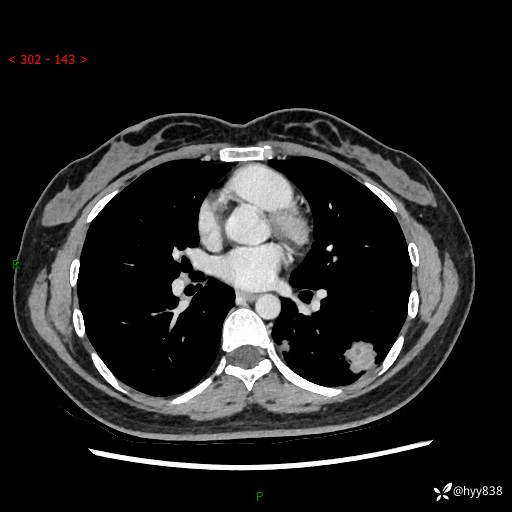

【患者信息】:36岁/女

【主诉】:左侧下胸部阵发性疼痛2周,乏力1周

【现病史及既往史】:患者自诉2周前饮酒后出现左侧下胸部阵发性疼痛,不随呼吸改变,无咳嗽咳痰、头晕头痛、咳血、呼吸困难等不适,于当地第一人民医院查胸部CT提示肺部感染,随后前往我院门诊给予抗感染(左氧氟沙星)治疗1周,自诉胸痛较前好转,感乏力、头晕,偶尔干咳,无咳痰,无发热、畏寒、胸闷、咯血、四肢酸痛、腹泻、腹痛等不适,门诊复查胸部CT提示:左肺下叶感染,病灶较前增加增大,遂以“肺部感染”收入我科。 起病以来,患者精神、饮食、睡眠可,大小便正常,体力体重无明显变化。

【检查】:胸部CT增强(外院平扫)